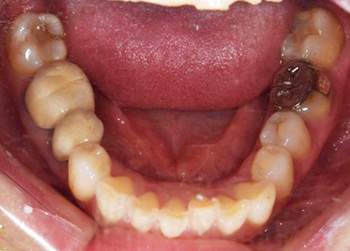

症例2

治療前

治療後

治療内容

奥歯はアマルガムという発ガン性があると言われている銀の素材を金銀シルバーインレーに変えました。前歯は金属を使用した歯でややまわりのご自身の歯より色がういていたので、周りの歯にあわせて透明感のある仕上がりのある材料にてやり変えました。

治療期間 1ヶ月

治療費 合計:990,000円 (内訳)

ジルコニアボンド:165,000円×6本

治療のリスク・副作用 被せ物を外すと、ご自身の歯が少ない場合は別途はを残すための処置が必要になることがあります。